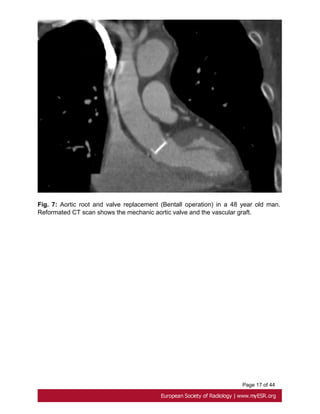

The original operation of aortic root replacement is the Bentall composite graft introduced

in 1968. This includes aortic root and valve replacement with either a biological

or a mechanical valve and requires coronary artery reimplantation . It stays the

standard because of a low rate of reoperation[15] but pose a risk of endocarditis and

thromboembolic disease demanding long-term anticoagulation. Fig. 7 on page 17

Fig. 7: Aortic root and valve replacement (Bentall operation) in a 48 year old man.

Reformated CT scan shows the mechanic aortic valve and the vascular graft.

Page 17 of44 Fig. 7: Aortic root and valve replacement (Bentall operation) in a 48 year old man. Reformated CT scan shows the mechanic aortic valve and the vascular graft.